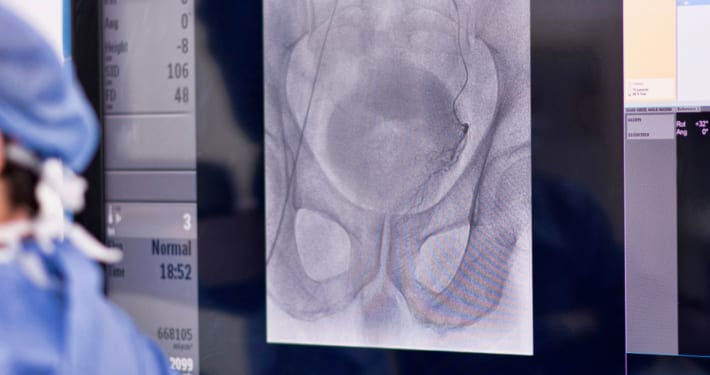

As radiologists, our job is to care for what we can see, using imaging technology in healthcare. Radiology of Indiana is a group of like-minded doctors who put patients first. We’re proud to offer you better options like longer hours, multiple locations and procedures that are often better than their alternatives.